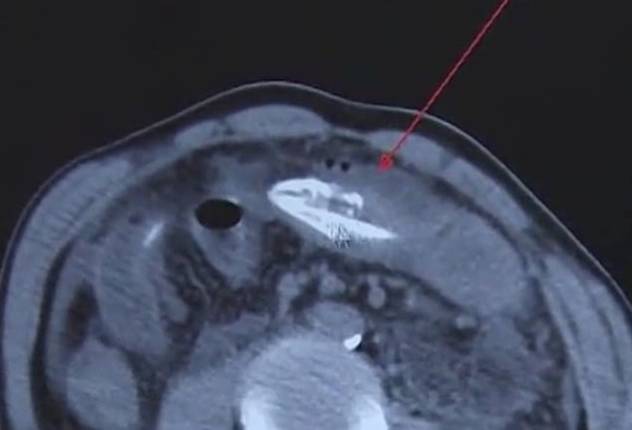

이름이 알려지지 않은 이 남성은 일주일 정도 복통에 시달렸다고 말했고, 의료진은 원인을 파악하기 위해 CT 촬영을 했다가 놀란 입을 다물지 못했다. 환자의 배 안에서 정체를 알 수 없는, 기다란 무언가가 발견됐기 때문이다.

환자의 배 속에서 복통을 유발한 정체는 다름 아닌 장어였다. 길이 50㎝의 거대한 장어는 환자의 배 속에서 발견됐을 당시 이미 죽은 상태였다.